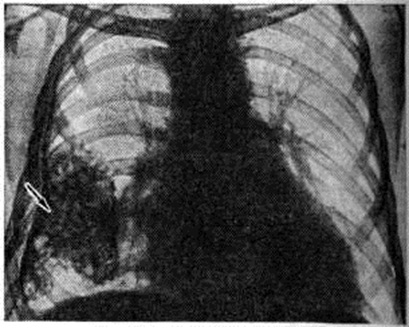

При накоплении больших количеств жидкости, когда последняя не умещается между висцеральной и диафрагмальной плеврой, она переходит в плевральные синусы. В этих случаях количество жидкости в плевральной полости обычно превышает 500 миллилитров чем выше расположена граница выпота, тем это количество больше. При переводе больного в горизонтальное положение жидкость растекается и прозрачность соответствующего лёгочного поля представляется пониженной, это так называемый феномен Ленка (смотри полный свод знаний Ленка феномен). Однако при небольшом количестве жидкости (менее 400 миллилитров) перевод больного в горизонтальное положение на трохоскопе не всегда позволяет получить положительный феномен Ленка, так как толщина слоя жидкости, растекающейся вдоль всей задней стенки грудной клетки, бывает недостаточной для того, чтобы появилась разница в прозрачности лёгочных полей. Лучшим способом выявления выпота в плевральной полости является исследование в латеропозиции на соответствующем боку. При этом жидкость растекается вдоль рёберного края, и по ширине образовавшейся пристеночной лентовидной тени можно судить о количестве выпота (рисунок 3). Если жидкости мало, целесообразно производить снимок в фазе выдоха; при этом полоска затемнения становится шире вследствие подъёма купола диафрагмы. Накопление очень большого количества жидкости в плевральной полости приводит к массивному затемнению всего лёгочного поля («тотальный плеврит») и резкому смещению срединной тени в противоположную сторону (рисунок 4).

Рис. 3.

Латерограмма больного с левосторонним плевритом: выпот образует пристеночную лентовидную тень (указана стрелками).